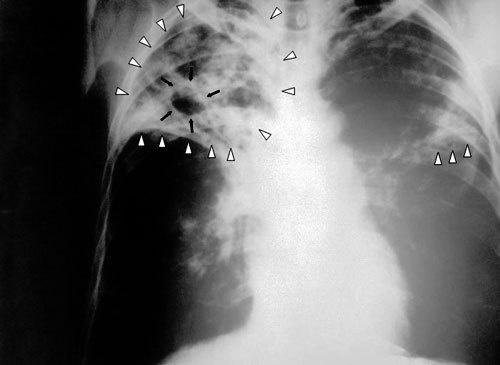

Рост заболеваемости туберкулезом на Северном Кавказе практически самый высокий в России

"Рост заболеваемости туберкулезом на Северном Кавказе практически самый высокий в России. В Чечне как уже зарегистрированных, так и новых случаев больше, чем в любом другом регионе России за исключением тех, где находятся учреждения пенитенциарной системы, в частности, в некоторых регионах Сибири", - рассказал корреспонденту "Кавказского узла" руководитель российского отделения ММК Семен Расин.

По данным врачей, сегодня в Чечне около 5 000 зарегистрированных больных туберкулезом. По словам Семена Расина, официальные цифры заболеваемости отражают лишь часть реальности. "Уровень заболеваемости туберкулезом очень значительный, причем уровень его выявляемости крайне низок. Очень плохой уровень подготовки специалистов. Есть энтузиасты, которые пытаются что-то сделать. А вот квалифицированных специалистов на местах практически нет - никто не хочет ехать работать в Чечню", - сетует руководитель российского отделения ММК.

На вопрос, в чем причины роста числа людей, больных туберкулезом, Семен Расин отвечает так: "Во время войны в Чечне не было никаких лекарств вообще. Все больные, которые находились на лечении от туберкулеза, перестали его получать, заражая при этом остальных. Во-вторых, туберкулез - болезнь социальная, болезнь бедности. Уровень безработицы в Чечне достигает 70% населения, а безработица среди молодежи - 85%".